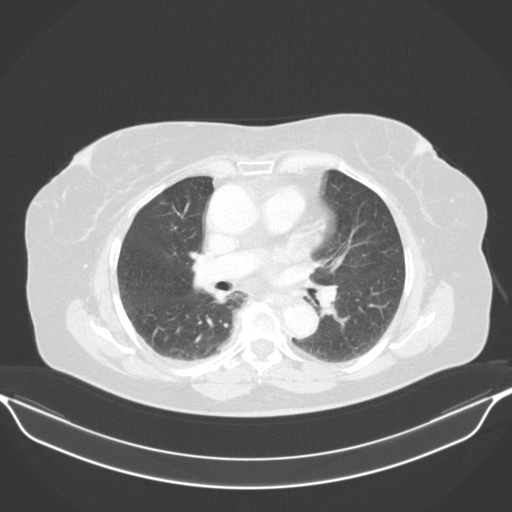

Image Grid

4Γ—3 grid: Rows show different image types (Original NATIVE, Reconstructed NATIVE, Original VENOUS, Generated VENOUS), Columns show windowing techniques (No Window, Lung Window, Mediastinum Window)

Lung window (WL -600, WW 1500 β†’ Low βˆ’1350, High +150)

Reconstructed NATIVE CT scan (cycle consistency)

Original VENOUS CT scan

Generated VENOUS CT scan (A→B translation)